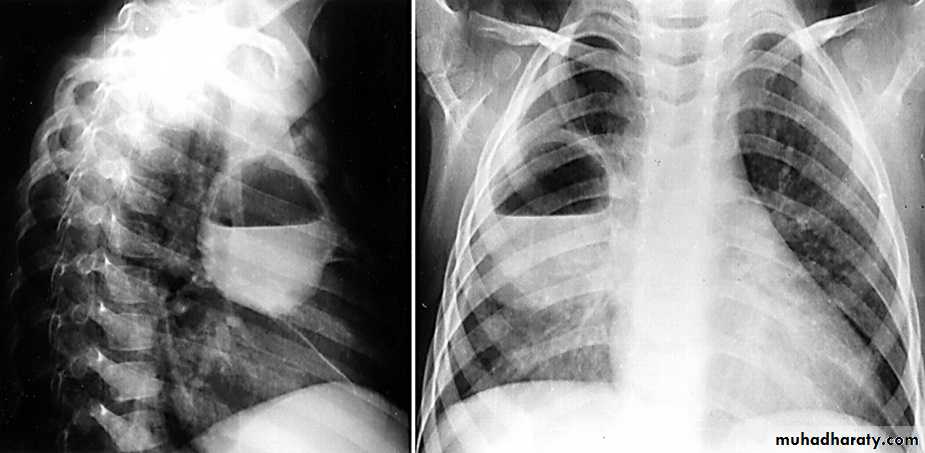

Radiologic anatomy of the RT lung lobes

Radiologic anatomy of the LT lung lobes

Lobes and fissures

This cut-out of a lateral chest x-ray shows the positions of the lobes of the right lung

On the left the oblique fissure is in a similar position but there is usually no horizontal fissure, and so there are only two lobes on the left.